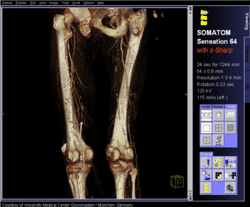

Снимки, созданные компьютерным томографом

А компьютерный томограф позволяет получить четкое изображение определенного среза тела. Сделав же "фотографии" нескольких таких срезов с шагом, скажем, в 1 миллиметр, мы получим очень качественное объемное, трехмерное изображение, которое позволяет увидеть в подробностях топографию органов пациента, локализацию, протяженность и характер очагов заболеваний, их взаимосвязь с окружающими тканями. Кроме того, чувствительность компьютерных томографов на порядок выше, чем обычных рентгеновских аппаратов: на рентгеновском снимке можно достаточно четко различить ткани, отличающиеся по степени поглощения рентгеновских лучей на 10-20%, а у современных компьютерных томографов этот показатель составляет 1-2%.

Реконструкция структуры тела на основе снимков компьютерного томографа: